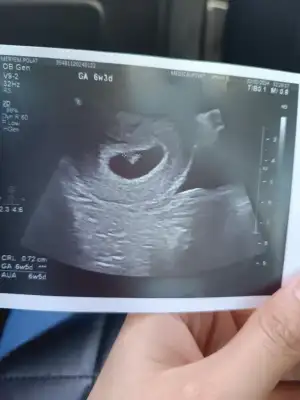

7+3 babada bi bakın yaaa🙏

Benimde bakarmısımız kızlar karından

Eklentiler